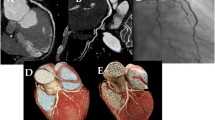

Coronary computed tomography angiography (CCTA) is a non-invasive diagnostic tool for detecting coronary heart disease that has low radiation exposure on patients compared with conventional angiography1,2. Despite its benefits, the radiation dose is still a concern among clinicians and CT scan manufacturers, and numerous techniques have been introduced to reduce its side effects on patients and medical personnel2.

The optimal heart rate for the procedure is between 65 and 75 beats per minute (bpm) because that range has the best diastolic phase to capture images of coronary arteries with minimal artifacts4,5,6. Currently, functional analysis of the heart can be performed using prospectively ECG-triggered sequential single cardiac phase CT images obtained through CCTA — derived from the fractional flow reserve (FFRCT)7 or by using myocardium analysis8. In contrast, retrospective ECG-gated CCTA is able to provide reconstruction of motion-free images with greater flexibility, thus allowing coronary arteries to be viewed at any R-R interval9.

CT examinations were performed using the 64-slice dual-source Siemens Somatom Definition Flash scanner (Siemens Medical Solution, Erlangen, Germany) according to parameters in Table 1. Tube voltage protocol was selected based on the patients’ BMI as indicated in Table 2. These parameters were standard protocol in IJN, and details like effective mAs and scanning time were tabulated in Table 3. Patients were positioned supine at the centre of the scanner gantry and a coronal topogram was obtained.

Based on the program, CT coronary calcium scoring and CCTA were performed, with the scanning range between the ascending aorta and heart apex to include the entire cardiac structure. In the CCTA scanning protocol, ECG-pulsing was used to steer the scan acquisition according to heart rhythm and to reduce radiation dose. ECG-pulsing window was set between 30% and 80% of the R–R interval (least motion for the coronary arteries) with a pitch ranging from 0.2 to 0.43, which was automatically adapted to the heart rate. For CT coronary calcium scoring, the ECG-pulsing window was set between 60% and 75% of the R-R interval with a pitch of 1.0. The ECG-pulsing kept the tube current at the highest level for user-defined R-R interval and used a lower tube current (20% reduction) for the remaining phase that eventually led to low radiation dose exposure.